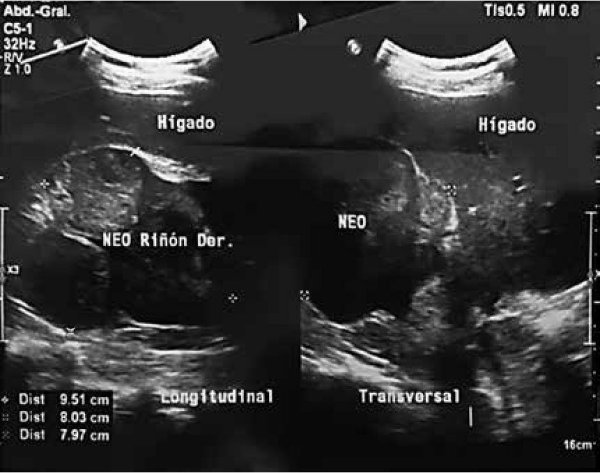

Ultrasonografía. Riñón derecho: reporta posible NEO riñón derecho (FIGURA 1).

FIGURA 1: Ecografía abdominal: Presencia de NEO en riñón derecho